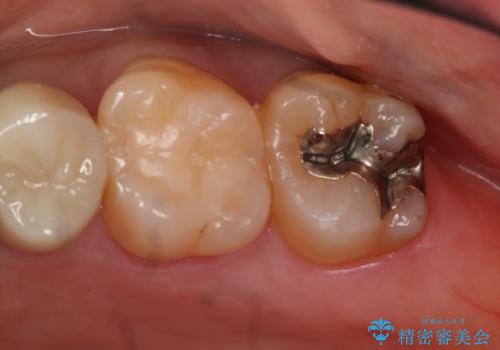

- 左上7番の銀歯のやり変えを希望された患者様です。

セラミックでの治療を希望されたため切削量などを考慮し、セラミックインレーでの治療を計画しました。

銀歯を除去し形態を整えたのち、印象しています。